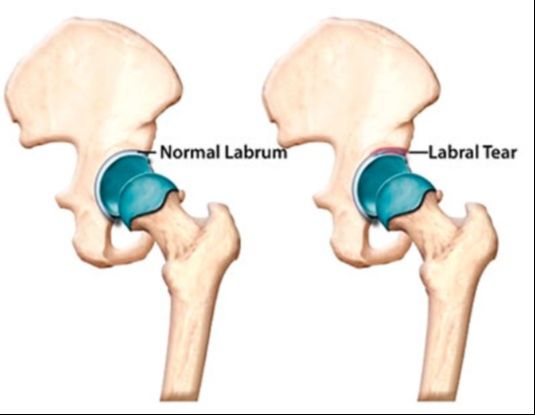

The second issue is the possibility of a hip labral tear. Due to my inability to have an MRI, this will prove difficult to diagnose. Made of tough cartilage, the labrum rings the hip’s socket, or acetabulum. The labrum is important to overall hip health and function. Specifically, the labrum:

- Facilitates the hip's range of motion, allowing the thigh to rotate in every direction, including forward, backward, inward, and externally

- Helps preserve proper alignment between the hip’s ball and socket

- Keeps synovial fluid, or joint fluid, within the hip joint capsule (synovial fluid reduces stress and friction and allows for smooth movement between the ball and socket)

In essence, the hip labrum is a ring of cartilage that provides both support and flexibility to the joint. When the labrum is damaged, the hips range of motion, alignment, and synovial fluid can be affected.